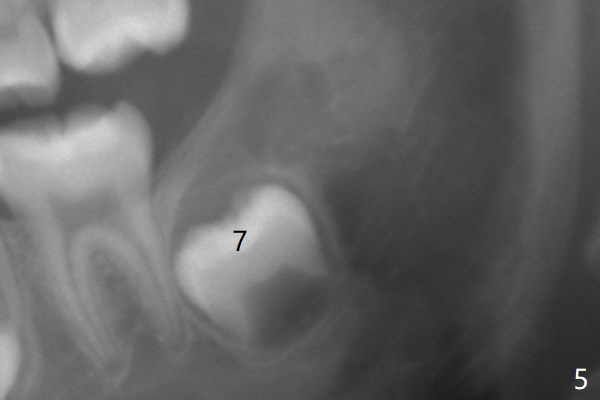

The tooth bud of LL8 appears to be close to that of LL7 at the age of 7.5 years (Fig.5).病人7岁时左下智齿牙胚好像已经接近7(图五与右侧比较)。现在左下七冠方仿佛有牙囊(图十四*)和隧道(T)。拔除智齿时,七牙合面骨质应该去除。术前将拍摄CT。